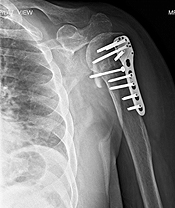

- Patient in the age group of 16 to 60 years: These constitute active population, and it is important to give them back, as near normal a shoulder as possible. For this, open reduction and internal fixation with plate and screws or a rod, is required.

We have an expertise in re-doing old operated fractures, and those which have not been treated properly, in the first place. The following are some of the examples: